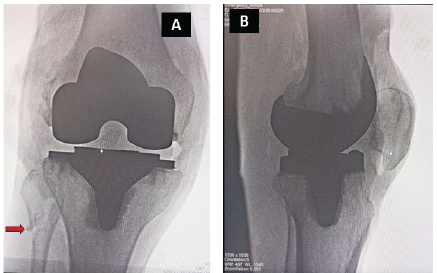

In addition, a posterolateral capsular release from the femur was performed. Perpendicular tibial osteotomy, with a 3° valgus correction angle for the distal femoral cut, was performed. Trapezoidal space in extension exhibited lateral tightness. Femoral cuts were made parallel to the trans epicondylar axis. A trapezoidal space observed in flexion, which is relatively diminished compared to extension. To create a rectangular space, posterolateral tibial capsular release is performed by subluxating the tibia anterior to the femur through knee hyperflexion and internal leg rotation, while positioning a Hohmann lever just posterior to the tibial intercondylar area. During this maneuver to expose the posterolateral aspect of the tibia, a faint audible indication occurred. We identified rectangular and symmetrical flexion and extension gaps. The trial implantation with a minimum-size spacer demonstrated stability in both flexion and extension (Fig. 2b). The original prosthesis was affixed with cement (Fig. 2c). Fluoroscopy revealed an iatrogenic fracture of the fibula head (Fig. 3). The knee exhibited stability throughout the range of motion. The post-operative radiographs exhibited no asymmetry (Fig. 4). No common peroneal nerve palsy was present (Fig. 5). He has undergone a standard physiotherapy regimen consisting of weight-bearing and range of motion exercises. Fracture union was evident at 3 months post-operation. He resumed his activities of daily living 3 months post-operation. The Knee Society Score has increased from 34 preoperatively to 90 postoperatively.

Figure 3: Intraoperative fluoroscopy images showing fibular fracture (red arrow).

Figure 4: Immediate post-operative X-ray of right knee (a); 2-month follow-up scanogram (b).